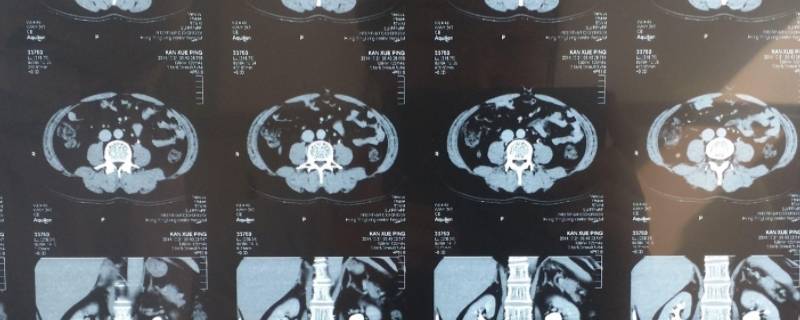

加强ct的药水大病报销吗

最佳答案根据情况而定。如果是在住院期间发生的ct费用,医疗保险一般可以予以报销;如果不是在住院期间发生的ct费用,只是看门诊做ct,那么医疗保险一般不予报销;需要注意的是,ct医疗费用严格意义上来说属于自费医疗费用,因此只有可保自费医疗费用的医疗保险才能进行报销,否则还需被保险人自己承担相关...

根据情况而定。如果是在住院期间发生的ct费用,医疗保险一般可以予以报销;如果不是在住院期间发生的ct费用,只是看门诊做ct,那么医疗保险一般不予报销;需要注意的是,ct医疗费用严格意义上来说属于自费医疗费用,因此只有可保自费医疗费用的医疗保险才能进行报销,否则还需被保险人自己承担相关医疗费用。